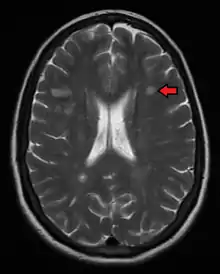

Magnetic resonance imaging (MRI) of the brain and spine may show areas of demyelination (lesions or plaques). Gadolinium can be administered intravenously as a contrast agent to highlight active plaques, and by elimination, demonstrate the existence of historical lesions not associated with symptoms at the moment of the evaluation.[70][71]

Central vein signs (CVSs) have been proposed as a good indicator of MS in comparison with other conditions causing white lesions.[72][73][74][75] One small study found fewer CVSs in older and hypertensive people.[76] Further research on CVS as a biomarker for MS is ongoing.[77]